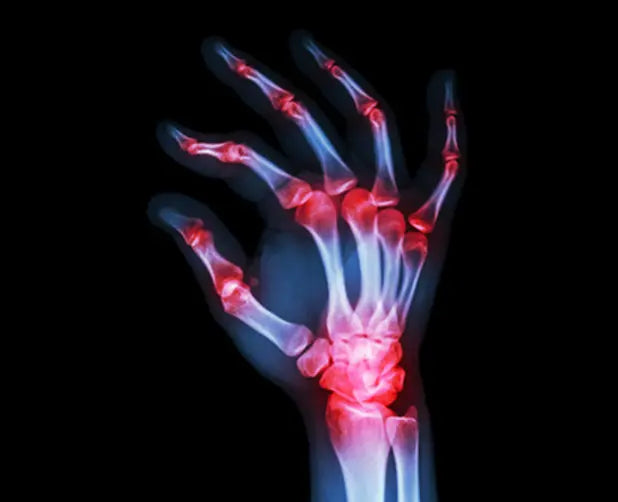

Autoimmunity can lead to a number of diseases such as multiple sclerosis, rheumatoid arthritis, and type 1 diabetes. In other words, it’s a bad thing!

Rheumatoid arthritis is an autoimmune condition where chronic inflammation damages the joints.